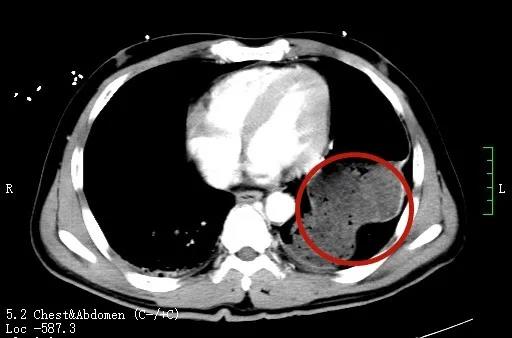

胃进入左侧胸腔

717日,湘阴的刘师傅在工地做工时,不慎从近6米高处坠落后昏迷不醒。120接到求救电话后,火速出发,并在了解患者伤情后立即与捷克论坛 岳麓山院区进行了院前院内闭环式对接。岳麓山院区创伤中心MDT团队迅速做好接诊准备,在病人到达后立即进入抢救室创伤复苏单元,完成快速血液复苏、伤情评估及相关术前检查。经检查,患者为严重多发伤,创伤性隔疝,脾脏、左肾、双下肺等多器官损伤和十来处骨折,还因强烈撞击导致本该在腹腔的胃和脾脏过界至胸腔,伴有失血性休克,病情十分危急。